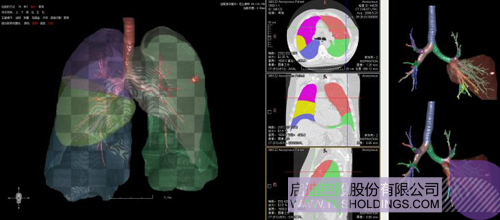

數(shù)字肺——肺結(jié)節(jié)手術(shù)規(guī)劃系統(tǒng)

完整的三維影像智能分析技術(shù);

完整的三維可視化以及相關(guān)建模、幾何分析技術(shù);

十多年一直從事醫(yī)學(xué)影像方面的研究與開發(fā),積累了大量的典型病例數(shù)據(jù)(>5萬人群),其中有相當(dāng)比例的多年(>6年)隨訪數(shù)據(jù)。